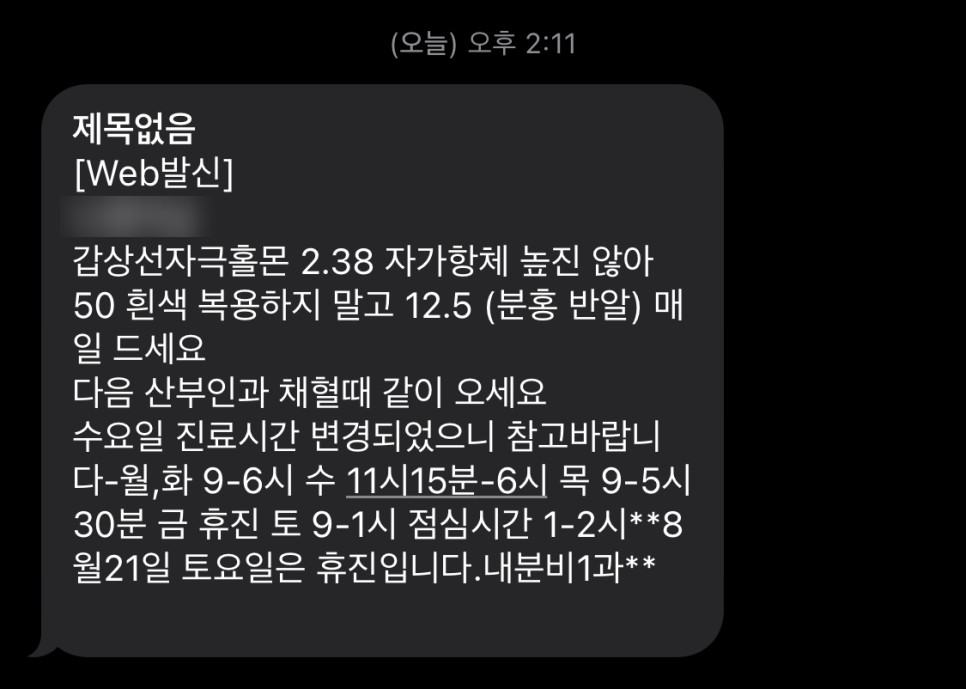

함유량이 다른 두 종류의 약을 처방받았고 며칠 뒤 검사 결과와 약 복용법을 문자로 다시 보내준다고 한다.

검사 결과가 나올 때까지는 산전검사 수치가 높았던 탓일까, 50마이크로그램?자리를 하루 한 알 먹으라고 했다.

이 알약들은 8주 시험에서 함량이 더 낮을 수도 있다. 이는 25마이크로그램이지만 반으로 나누어서 12.5마이크로그램이다.

며칠 후 스캔 결과 메일!

왜 이렇게 수치가 떨어진거야? 정상범위 안에 있어!!!!!

그래도 작은 용량의 알약을 먹으라고 하네.

정상 범위 안에 있지만 그래도 높은 축에 속하기 때문이다.

갑상샘약 복용법 갑상샘 호르몬은 새벽오전 분비가 모두 끝난다고 한다.오전 9시 이내에 빈속에 약을 복용하고 아침은 약 1시간 뒤부터 먹는 것이 좋다.